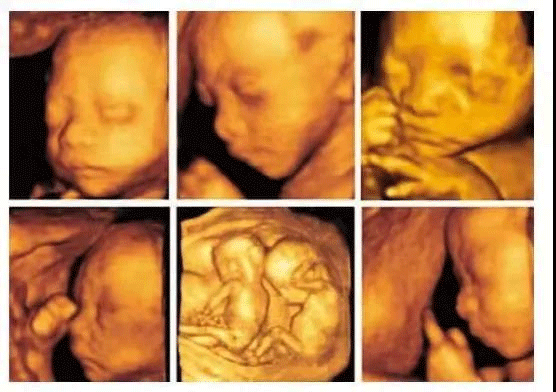

回答:孕期四维彩超是超声检查的一种,其成像技术能够让孕妇更加清晰的观察宝宝的生长发育情况。

除了对胎儿进行常规检查外,四维彩超和B超的区别在于其图像更加立体,能够对胎儿头面部立体成像,帮助医生动态观察宝宝神经系统情况,是孕早期胎儿排畸的重要检查手段,高档次的四维检查,还添加了时间维度参数,可以实时掌握胎儿活动图像。

在临床上,四维彩超的全称为四维彩色超声诊断仪,是目前世界上先进的超声检查设备,为胎儿是否有先天性心脏病、脊柱裂畸形等提供准确的科学依据,孕妇可以及早发现及时做处理,达到优生优育的目的。

2、通过观察宝宝的脑部发育,从胎头的形状、脑组织(包括丘脑、小脑、小脑蚓部、颅后窝池等)、中线距两侧颅骨板的距离等,精准侧脸胎儿脑部情况;

3、面部是否存在畸形,我们都知道四维彩超的作用就是能够将胎儿的全身情况以非常清晰的形式展现出来,所以医生通过观察胎儿面部,测量双眼与眼眶是否等大、眼距信息、硬腭、软腭等,诊断脸部发育是否畸形;